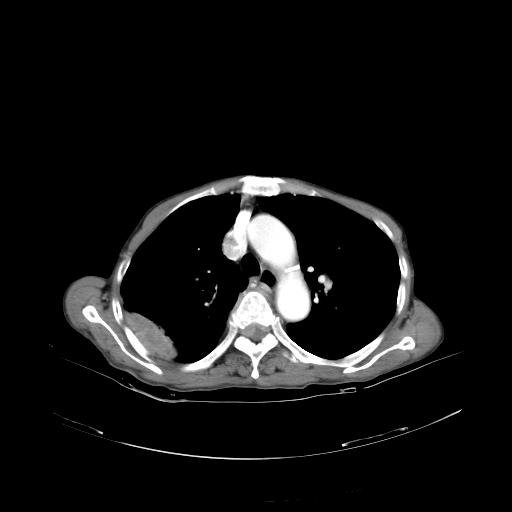

女,72岁,咳嗽一周余,突发右下肢无力二天。

pe:bp-140、80mmhg,精神可,伸舌居中,右上肢肌力正常,右下肢肌力0级,巴氏征+

来院做头颅+胸部ct平扫

遂加作增强:

胸部病变平扫35hu,增强强化至70hu

这个病人首先是胸部病变的定位到底是肺内还是肺外。仔细观察块影位于胸膜下,与胸膜间有透亮带,且近端血管未见明显推移而是引流样改变,形态分叶,说明这个病灶位于肺内胸膜下。很可能是腺癌,腺癌最易致颅内高密度转移灶。局部胸膜有侵犯。

本例颅内见多发大小不等高密度灶,有强化及水肿;另外,胸锁关节层面可能是第四胸椎及右侧肋骨起始部骨质欠连续,椎旁软组织肿胀,建议调骨窗观察。

诊断:右下肺癌伴颅内、胸椎、肋骨转移可能性最大。